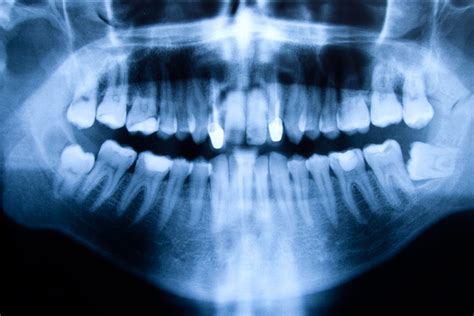

Un quiste dental es una pequeña bolsa llena de líquido, aire o células que se forma en relación con un diente. Por lo general, se detectan en radiografías de rutina y, aunque suelen ser benignos, es importante tratarlos para evitar complicaciones. Este problema es más común de lo que imaginas. Si tú o alguien que conoces tiene un quiste dental, no te alarmes, pero sí es fundamental que acudas a tu odontólogo lo antes posible.

Aunque la mayoría de los quistes dentales son benignos, en raras ocasiones, pueden volverse malignos. Por eso, es vital realizar visitas regulares al dentista, incluso si no tienes síntomas, para detectar cualquier quiste mediante un estudio radiológico y determinar su naturaleza a través de una biopsia y estudio microscópico si es necesario.